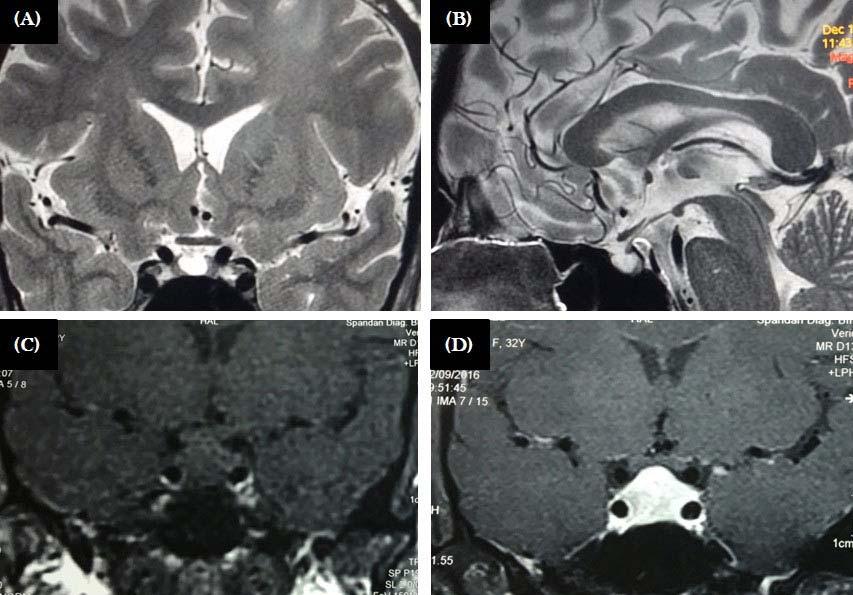

Majority of the patients had abnormal appearances of the HP region on MRI (Table 5) (Figs 1&2). Empty sella with varying thickness of the remaining pituitary tissue was the commonest abnormality noted (28 patients, 52.8% of the cohort). Only 3 patients (5.66%) had apparently normal looking HP region. Hypophysitis was diagnosed retrospectively in 1 lady with ES, whose previous MRI was consistent with hypophysitis11. One male with hypophysitis

Fig 2 — Upper panel: MRI of patients with craniopharyngioma. Mixed solid-cystic lesion with cystic component being hyperintense in both T1 (A) and T2 (B) weighted sequences

Lower panel: Patient with hypothalamic mass, that is isointense in T1 (C) with intense contrast enhancement (D)